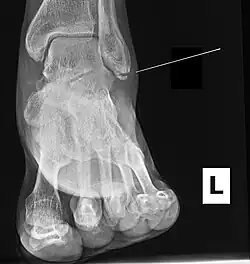

| Radiograph showing a Maisonneuve fracture of the proximal fibula | |

The Maisonneuve fracture is a spiral fracture of the proximal third of the fibula associated with a tear of the distal tibiofibular syndesmosis and the interosseous membrane. There is an associated fracture of the medial malleolus or rupture of the deep deltoid ligament of the ankle. This type of injury can be difficult to detect.[1][2]